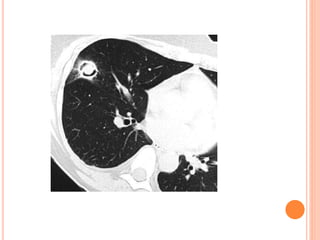

This document summarizes aspergillosis, including invasive pulmonary aspergillosis (IPA), chronic necrotizing aspergillosis (CNA), and aspergilloma. Aspergillus is a common mold that can cause a variety of pulmonary diseases. IPA predominantly affects immunocompromised patients and presents as pneumonia. Diagnosis involves tissue biopsy, galactomannan testing, and imaging. Voriconazole is recommended treatment. CNA occurs in patients with underlying lung disease and is characterized by slow lung tissue invasion. Itraconazole is effective treatment. Aspergilloma involves a fungus ball in a pre-existing lung cavity.